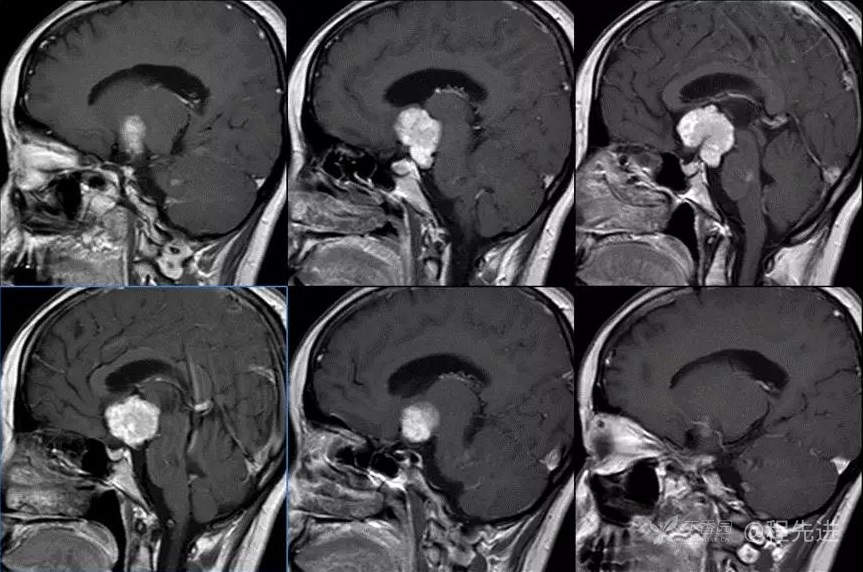

图像依次为T1横断位、T2横断位、T2FLAIR横断位、T2冠状、T1矢状、T1增强横断、矢状、冠状位